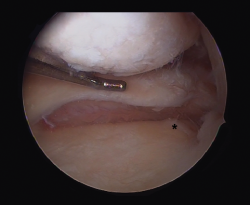

Meniscal ramp lesions

Although recently greater importance is being placed on the presence of so-called meniscal ramp lesions (Figure 3), with an estimated incidence of up to 23.9%(19) associated to ACL rupture, these lesions were already described by Strobel(20) in 1988 as a particular type of meniscal injury associated to ACL rupture and affecting the peripheral insertion of the posterior horn of the medial meniscus. These injuries are also referred to as hidden lesions of the posterior horn of the medial meniscus, since they may go undetected in the MRI studies(21). From the biomechanical perspective, ramp lesions of the knee with ACL rupture increase anterior translation of the tibia, internal and external rotation, and pivot shift. If not repaired, rotational stability following reconstruction of the ligament likewise is not fully restored(22).

Figure 3. Repair of a lesion of the posterior ramp of the medial meniscus (*) adopting a posteromedial arthroscopic approach. Trans-notch view from the anterolateral port. Working cannula in the posteromedial port (PMP). IFC: internal femoral condyle. Right knee.